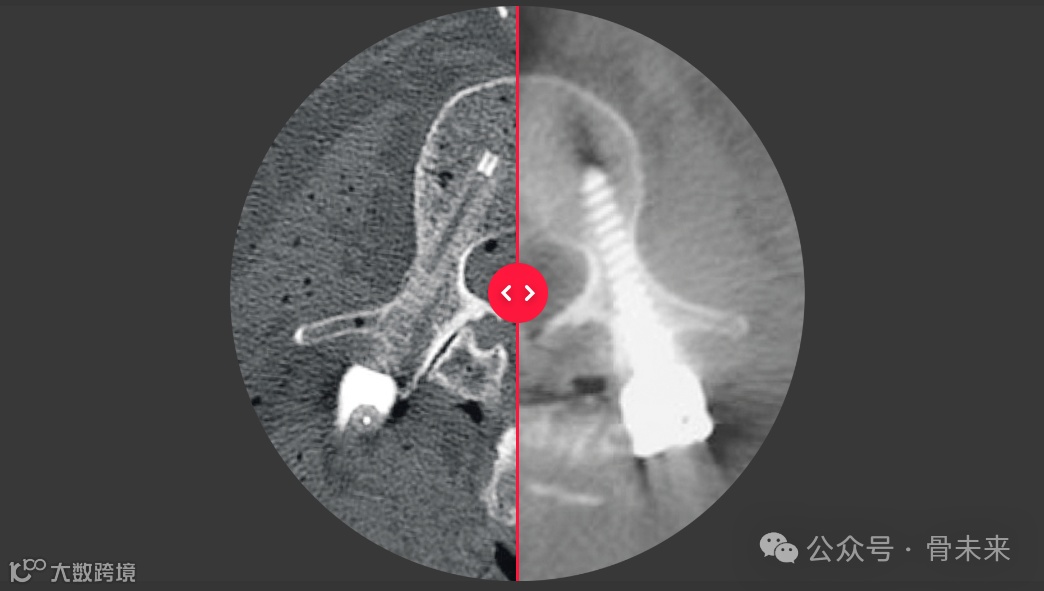

▲图:左:BlackArmor® 碳/PEEK;右:钛

icotec 公司开发的非金属、可透放射线的 BlackArmor® 材料具有生物相容性,并已成功植入超过15年。它在 X 射线下呈半透明状,有助于对肿瘤复发和骨融合的护理部位进行清晰的术后评估,可以更好地从健康组织中找到肿瘤,并优化放射治疗计划和肿瘤治疗方案。

最佳呈现组织结构(骨骼和神经):使用 X 射线、计算机断层扫描和磁共振成像进行术后评估;